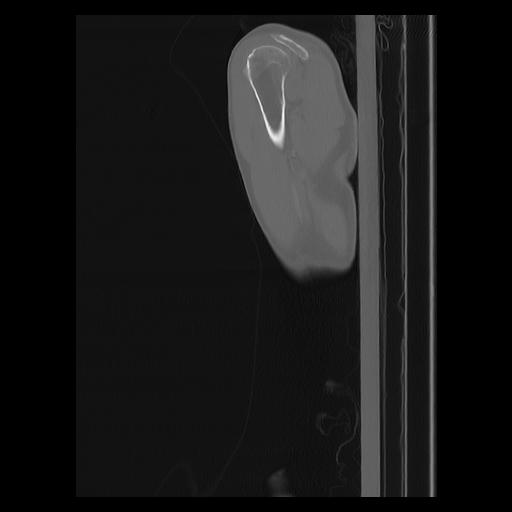

33 PULMON,CE,Sagittal,3.000,PULMON,Sagittal,